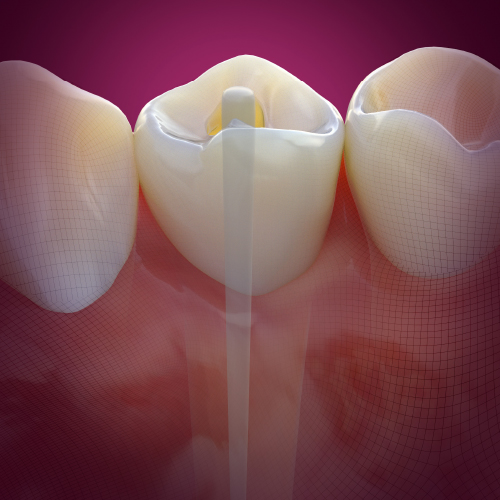

Early Diagnosis and Treatment of Asymptomatic Vertical Enamel and Dentin Cracks

Wednesday, November 23, 2022

This Compendium eBook offers a continuing education (CE) article that presents a systematic approach for the early diagnosis and treatment of asymptomatic vertical enamel and dentin cracks based on current evidence. Download to earn 2 FREE CEU now!